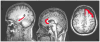

Interventions: Echo-planar and high-resolution T1-weighted images were acquired using 3-T scanners. Regions of interest (ROI) were drawn bilaterally for the hippocampus, anterior cingulate cortex (ACC), and dorsolateral prefrontal cortex and were used to extract time series data. Blood oxygenation level-dependent data from each ROI were used as reference functions for correlating with all other brain voxels. Interhemispheric functional connectivity was assessed for each participant by correlating homologous regions using a Pearson correlation coefficient. Patient functional and neurocognitive outcomes were assessed approximately 6 months after injury.

Results: Patients showed significantly lower interhemispheric functional connectivity for the hippocampus and ACC. Controls demonstrated stronger and more focused functional connectivity for the hippocampi and ACC, and a more focused recruitment of the default mode network for the dorsolateral prefrontal cortex ROI. The interhemispheric functional connectivity for the hippocampus was correlated with delayed recall of verbal information.